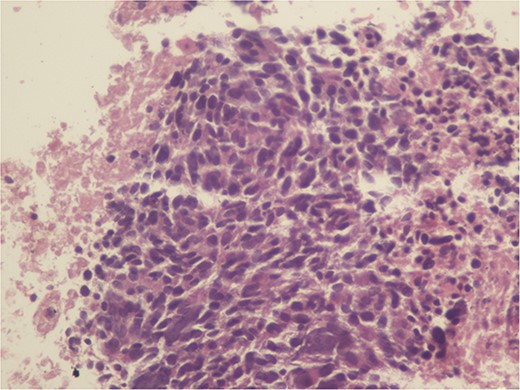

A 59-year-old woman presented with complaints of abdominal pain and abdominal distension for about a month. There was no known systemic disease and no history of previous abdominal surgery. It was learned that the patient had been admitted to the emergency department in another center one month ago with the current complaints and was discharged after medical treatment. Physical examination at the time of admission revealed abdominal distension and diffuse minimal tenderness with no signs of peritoneal irritation. Laboratory tests revealed that hemogram and biochemical parameters were within normal limits, but one of the tumor markers, the patient’s CA 19-9 level was significantly elevated at 855 U/ml (normal range: 0–37 U/ml). Contrast-enhanced CT scan showed a 10×10 cm heterogeneous mass in liver segments 4B-5, extending to segment 6, and free fluid adjacent to the liver and irregular liver contours. Borders of the gallbladder could not be seen. Soft tissues forming nodular mass formation were detected on the omental surfaces (Fig. 1). Computed tomography examination performed at the center where the patient was admitted as an emergency one month ago revealed hypodense lesions measuring 10×8 cm in size in the left lobe of the liver, protruding into the inferior perihepatic area, and 3.5 cm in diameter in segment 5 of the right lobe with no significant contrast enhancement after intravenous injection of contrast material. Perihepatic ascites was not detected and gallbladder size, wall thickness and lumen were normal (Fig. 2). In the light of the radiologic findings, a pre-diagnosis of progressive gallbladder malignancy was considered. The patient was hospitalized in the General Surgery ward for further investigation and treatment. Because of the presence of ascites causing abdominal distension, a percutaneous ascites drainage catheter was placed and 5000 cc ascites drainage was performed. Cytologic examination of the ascitic fluid revealed cell groups with unclear three-dimensional cytonuclear detail among lymphocytes and mesothelial cells with reactive atypia and malignancy was considered suspicious. With the current radiologic and cytologic findings, inoperable metastatic gallbladder carcinoma was considered. Medical treatment was decided by the multidisciplinary oncology council and 18G needle tru-cut biopsy was performed from the 10×10 cm mass adjacent to the gallbladder for definitive tissue diagnosis and adjuvant treatment planning. Histopathologic examination revealed a diagnosis of neuroendocrine carcinoma (NEC) (Fig. 3). Immunohistochemical examination revealed strong staining of tumor cells with CD56 (Fig. 4), synaptophysin (Fig. 5), chromogranin A (Fig. 6), and Ki67 index was >90% (Fig. 7). Weak staining was observed with CK19, CK7, and CDx2, but no staining was observed with CEA and CK20. Morphologic findings were compatible with small cell type. Etoposide and cisplatin chemotherapy was planned but the patient’s general condition deteriorated progressively. The patient couldn’t start chemotherapy and unfortunately resulted in mortality on the 20th day of hospitalization.

The diagnosis of small cell NEC typically involves a combination of clinical evaluation, imaging studies, and histopathological examination. Immunohistochemical staining is crucial for confirming neuroendocrine differentiation, with common markers including synaptophysin, chromogranin A, and CD56. A high Ki-67 index is indicative of the aggressive nature of small cell NEC [2].